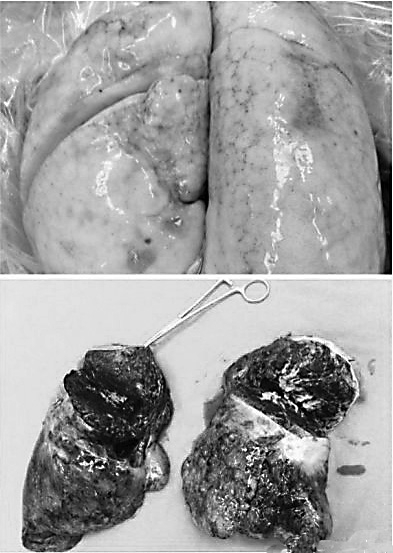

已经纤维化的肺

健康的肺和尘肺病患者的肺部

尘肺病是由于在生产活动中长期吸入生产性粉尘,并在肺内沉积而引起的以肺组织弥漫性纤维化为主的全身性疾病。